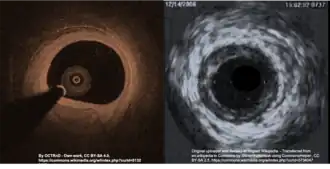

Intracoronary imaging

Intracoronary imaging (ICI), consisting of intracoronary optical coherence tomography (OCT) and intravascular ultrasound (IVUS) can help distinguish SCAD from an atherosclerotic lesion when it is difficult to do so with angiography.[19] ICI techniques provide a direct view of the walls of the coronary artery to confirm SCAD, but may actually worsen the dissection as the probes are inserted into the damaged area.[4] ICI confers a 3.4% risk of iatrogenic dissection in people with SCAD compared to 0.2% risk in the general population.[4] Between the two ICI methods, OCT - a newer technique - has superior spatial resolution than IVUS and is the preferred technique if ICI is required,[4] but the need to inject extra contrast with OCT poses risk for worsening the dissection.[14]